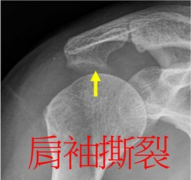

如何区分肩周炎和肩袖撕裂呢?

郑州肩周炎专科医院,河南治疗肩周炎专家讲到如果您的肩关节疼痛,肩关节的活动范围明显减…[详情]